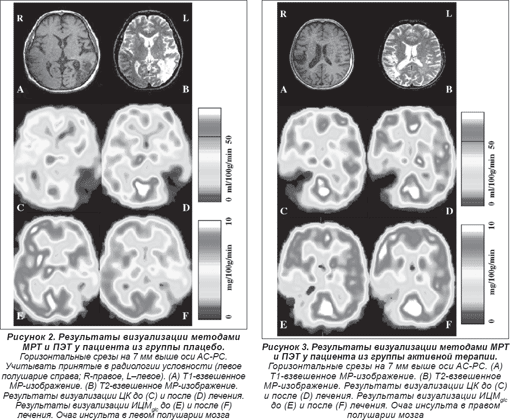

Т1- и Т2-взвешенные результаты визуализации методом МРТ (см. рисунки 2А и 2В, 3А и 3В) отчетливо показали расположение патологического очага в ткани головного мозга, а метаболические и гемодинамические данные ПЭТ продемонстрировали снижение ЦК в зоне инсульта до лечения (рисунки 2С и 2Е, 3C и 3E) при относительном его увеличении после лечения (рисунки 2D и 3D), а также исходный уровень и изменения метаболизма глюкозы (рисунки 2F и 3F).

Наибольшее увеличение кровотока после терапии в группе плацебо обнаруживалось в среднем мозге (13,76 ± 4,92%), мосте (8,89 ± 4,16%) и мозжечке (9,54 ± 4,12%), в то время как в группе активной терапии таковое определялось в тех же структурах (средний мозг — 33,08 ± 6,54%, мост — 18,59 ± 8,31%, мозжечок — 28,26 ± 7,75), а также неповрежденном таламусе (36,39 ± 17,55), хвостатом ядре (37,29 ± 15,38%) и зоне инсульта (33,89 ± 2,69%) (таблица 2, рисунки 2 и 3). Тест ANOVA с трехсторонним взаимодействием показал несомненную тенденцию к увеличению показателей ЦК после лечения при особой заинтересованности таламуса (F(5,55) = 1,81; p < 0,12). Тем не менее, обусловленные терапией изменения в контрлатеральной гемисфере после применения винпоцетина (Кавинтона®) характеризовались отчетливой тенденцией к более выраженному повышению (величины p в пределах от 0,12 до 0,46), нежели в группе плацебо (от 0,50 до 0,99 соответственно) (таблица 2). Сравнение различий показателей кровотока (группа плацебо/до и после лечения и соответствующие величины в группе получавших винпоцетин (Кавинтон®)) также показало четкую тенденцию, а именно что интенсификация кровотока в группе активной терапии характеризуется тенденцией к отчетливому превышению таковой в группе плацебо (для базальных ганглиев, таламуса, среднего мозга, затылочной и лобной коры, а также всего незаинтересованного полушария p < 0,25).

Увеличение показателей ЦК в группе получавших винпоцетин (Кавинтон®) было в различных участках головного мозга неоднородным. В контрлатеральном полушарии показатель был явно выше в большинстве мозговых структур. Увеличение было наибольшим в тканях таламуса, хвостатого ядра и среднего мозга. При этом винпоцетин (Кавинтон®) повышал наиболее заметно ЦК в области хвостатого ядра (37,29%), таламуса (36,39%) и среднего мозга (3,08%), далее в ряду располагались мозжечок, лобная область коры, путамен и затылочная кора больших полушарий. Эти структуры головного мозга соответствуют зонам, где обнаруживается наибольший захват [11C]-винпоцетина (Кавинтона®) как у лабораторных обезьян [21], так и у человека [22, 23, 25]. Этот факт может указывать на выраженную связь фармакологических и физиологических эффектов препарата в некоторых структурах мозга. В действительности, усиление перфузии в неповрежденной ткани после ишемического инсульта было описано ранее на основании определения параметров регионального церебрального кровотока методом ПЭТ (см. напр. [51]).

В заинтересованном полушарии имело место увеличение ЦК во всех структурах как после контрольной инфузии, так и после введения винпоцетина (Кавинтона®). Аналогично данным в отношении незаинтересованного полушария, в большинстве структур увеличение ЦК после инфузии винпоцетина (Кавинтона®) было более заметным, нежели в результате введения изотонического солевого раствора. Это явление было особо выраженным в зоне инсульта (33,89%), таламусе (21,75%), среднем мозге (24,32%) и мозжечке (25,94%), что указывает на перераспределение кровоснабжения между структурами головного мозга под влиянием винпоцетина (Кавинтона®).